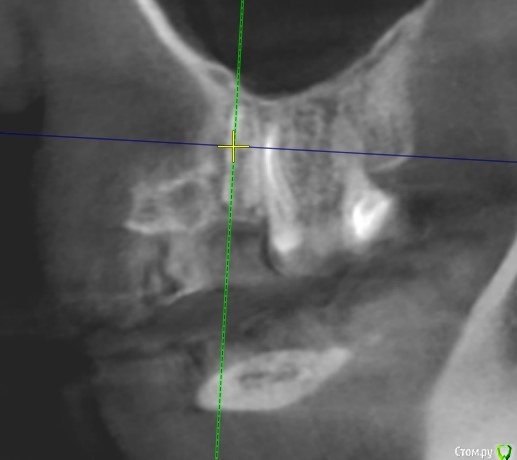

Tatiana72 Опубликовано 27 октября, 2020 Автор Поделиться Опубликовано 27 октября, 2020 Добрый вечер!Выкладываю скрины срезов Ссылка на исследованиеhttps://yadi.sk/d/ViQR0U6R2QjHzg Ссылка на комментарий

Дмитрий М Опубликовано 28 октября, 2020 Поделиться Опубликовано 28 октября, 2020 Добрый вечер!Выкладываю скрины срезовImage4.jpgImage5.jpgImage9.jpg Ссылка на исследованиеhttps://yadi.sk/d/ViQR0U6R2QjHzg не волнуйтесь всё хорошо, по КТ корень зуба не задетесть небольшой очаг разряжения на одном из апексов, обратитесь к стоматологу 1 Ссылка на комментарий